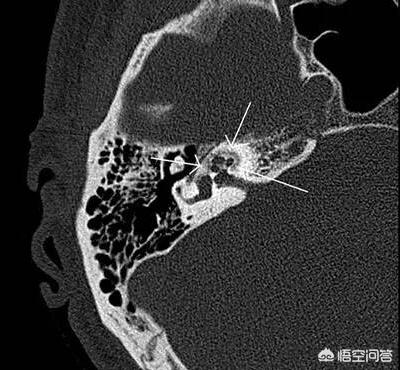

什么是耳硬化症?经过临床观察和大量内耳病理切片研究,这种病的病理变化是由于内耳骨迷路靠近卵圆窗部位的正常骨质被吸收而被一种富于血管的新生海绵状骨质所代替。这种海绵状新生骨灶逐渐骨化变硬,所以习惯上称作“耳硬化症”。这种病理性骨灶逐渐蔓延,侵及镫骨底板,使它固定在卵圆窗上。声音由鼓膜、听骨传达到这里,就不能再向内耳传过去了。如果这种病理骨灶向内蔓延及内耳,引起耳蜗损害或前庭蜗神经变性,称作“耳蜗性耳硬化症”。

耳硬化症是一种病因尚未明确的疾病,与遗传、种族、代谢紊乱及内分泌障碍有关,病理表现为多形的骨病,骨迷路发生反复的局限性骨质吸收,并被血管丰富的海绵状新生骨质替代,继而血管减少,骨质沉着形成骨质硬化病灶,故称“耳硬化”。当侵犯卵园窗时,可引起镫骨固定,失去传音功能,出现听力进行性减退。耳硬化症的发病率与人种有很大关系,白种人发病率高,黑种人发病率最低,黄种人介于两者之间。发病年龄以中青年较多,好发年龄20-40岁。手术治疗是提高听力最有效的措施,镫骨手术为现代耳显微外科首选手术方式 ,具体手术方式包括CO2激光镫骨切除术、piston人工镫骨术,半规管开窗术等。不适于或者不愿接受手术患者可以酌情选配适宜的助听器。